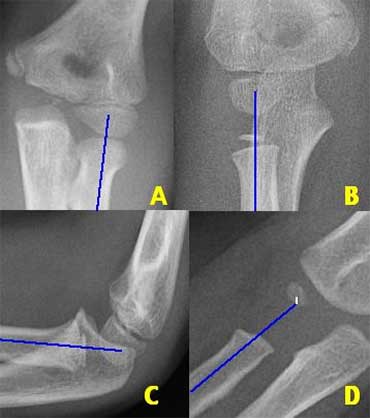

There are two important lines which help in the diagnosis of dislocation and fracture .

These are the Radiocapitellar line and the Anterior humeral line.

Radiocapitellar line

A line drawn through the centre of the radial neck should pass throught the centre of the capitellum, whatever the positioning of the patient, since the radius articulates with the capitellum (figure).

In dislocation of the radius this line will not pass through the centre of the capitellum.

On the left we see, that the radiocapitellar line goes through centre of the capitellum on every radiogragh even though C and D are not well positioned.

Notice supracondylar fracture in B.

On the left more examples of the radiocapitellar line.

The right lower image shows an obvious dislocation of the radius.